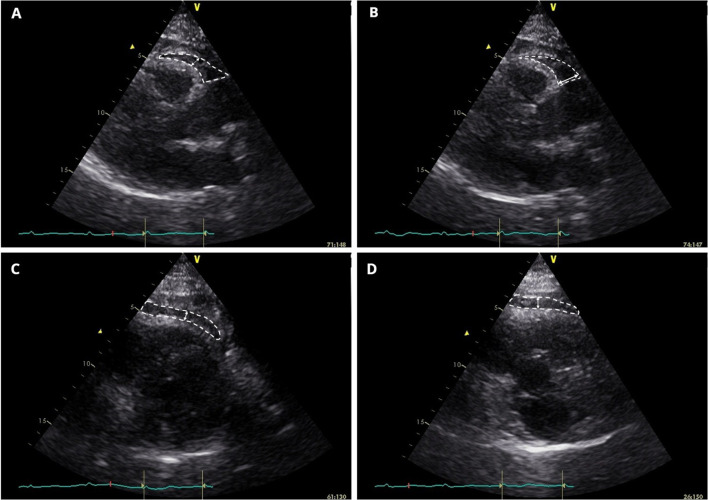

All echocardiograms were performed after coronary angiography, with the patient positioned in left lateral decubitus. Echocardiographers were blinded to the coronary angiography results. Obtained images were then exported to a computer database and processed with EchoPAC® Clinical Workstation Software version 113 (General Electric, Healthcare, Chicago, Illinois) by the same cardiologist, who was blinded to clinical data and angiographic results. Exams were conducted using a General Electric Vivid S6 Ultrasound system and 3Sc-RS tissue harmonics transducer operating with a frequency of 1.4/3.4 MHz. EF measurement included the method proposed by Iacobellis and Willens [19] (PLAXFW) (Fig. 1a). Still, in PLAX view, we positioned the caliper just to the right of the aortic annular plane at the basal region of the RV (PLAXB) (Fig. 1b), as suggested by the same authors [19]. Using parasternal short-axis (PSAX) view, we measured EF at mid-ventricular level (PSAXMV) (Fig. 1c) and in the basal segment of the RV (PSAXB) (Fig. 1d), taking into account the greater thickness of EF in both regions. We also calculated the average value of EF thickness and local mean EF thickness at mid-ventricular and basal levels. EF thickness was measured in millimeters (mm).

Fig.1.

Epicardial fat (within white dashed shape) is identified as the echo-lucent space between the outer myocardium and echo-dense visceral pericardium. The largest local epicardial fat thickness is measured (white arrows). Panel A-B. Parasternal long-axis view, right-ventricular free-wall and basal epicardial fat measurement, respectively. Panel C-D. Parasternal short-axis view, right mid-ventricular and basal epicardial fat measurement, respectively